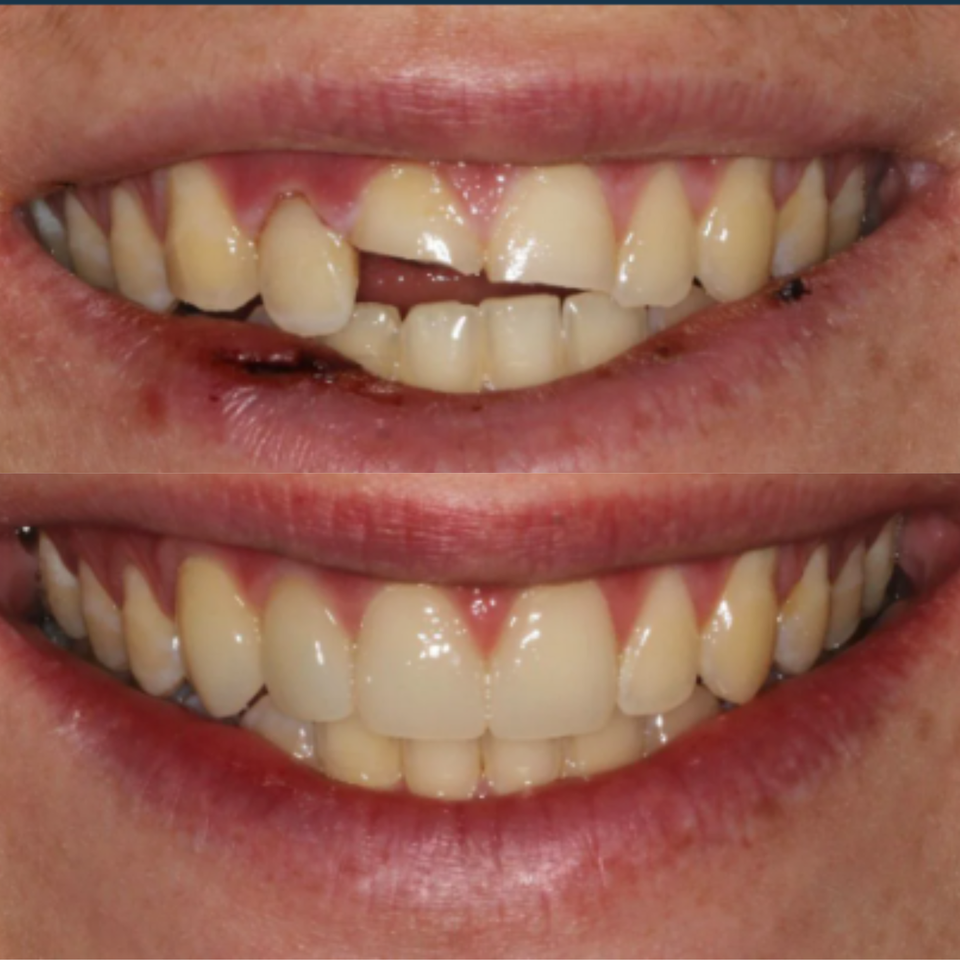

At our practice, we recently helped a patient restore their smile after experiencing a complex dental issue involving a periodontal infection and a root fracture. To fully restore both health and aesthetics, we recommended a comprehensive implant-based solution.

The treatment process included:

• Extraction and Bone Grafting to properly prepare the site for implant placement

• Implant Placement with Soft Tissue Grafting to ensure long-term stability and natural-looking gum contours

• Provisional Implant-Supported Crown to maintain appearance and function during healing

• Final Implant-Supported Crown, custom-designed for strength, beauty, and seamless integration

We are extremely proud of the final result, and most importantly, our patient is now enjoying a healthy, confident smile once again.